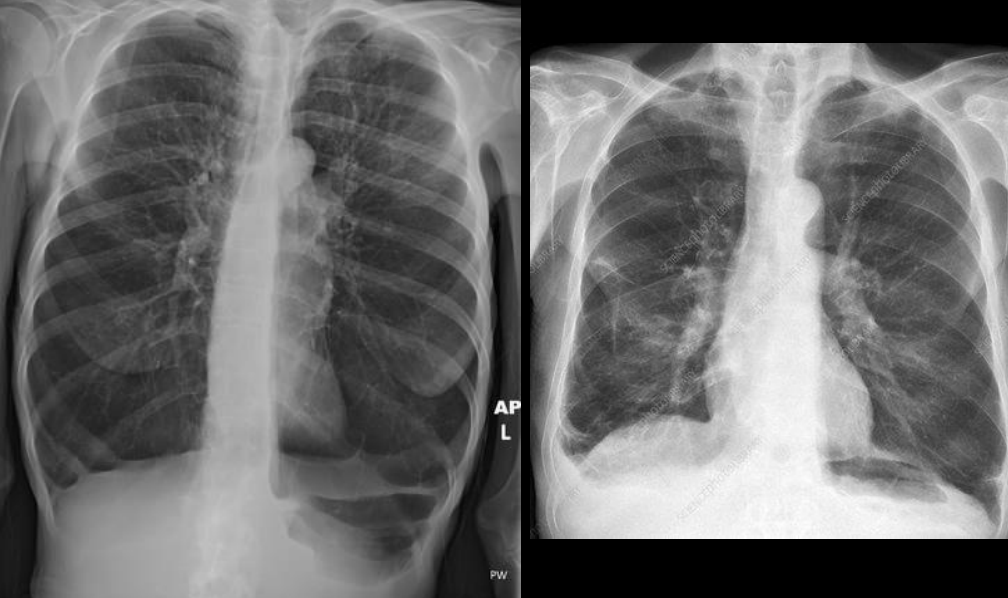

RX ENFISEMA

Aplamaniendo de diafragma: se alcanzan a ver las 12 costillas

Corazón en gota

Hiperinsuflación

Hiperlucidez pulmonar

Disminución de marcas broncovasculares periféricas